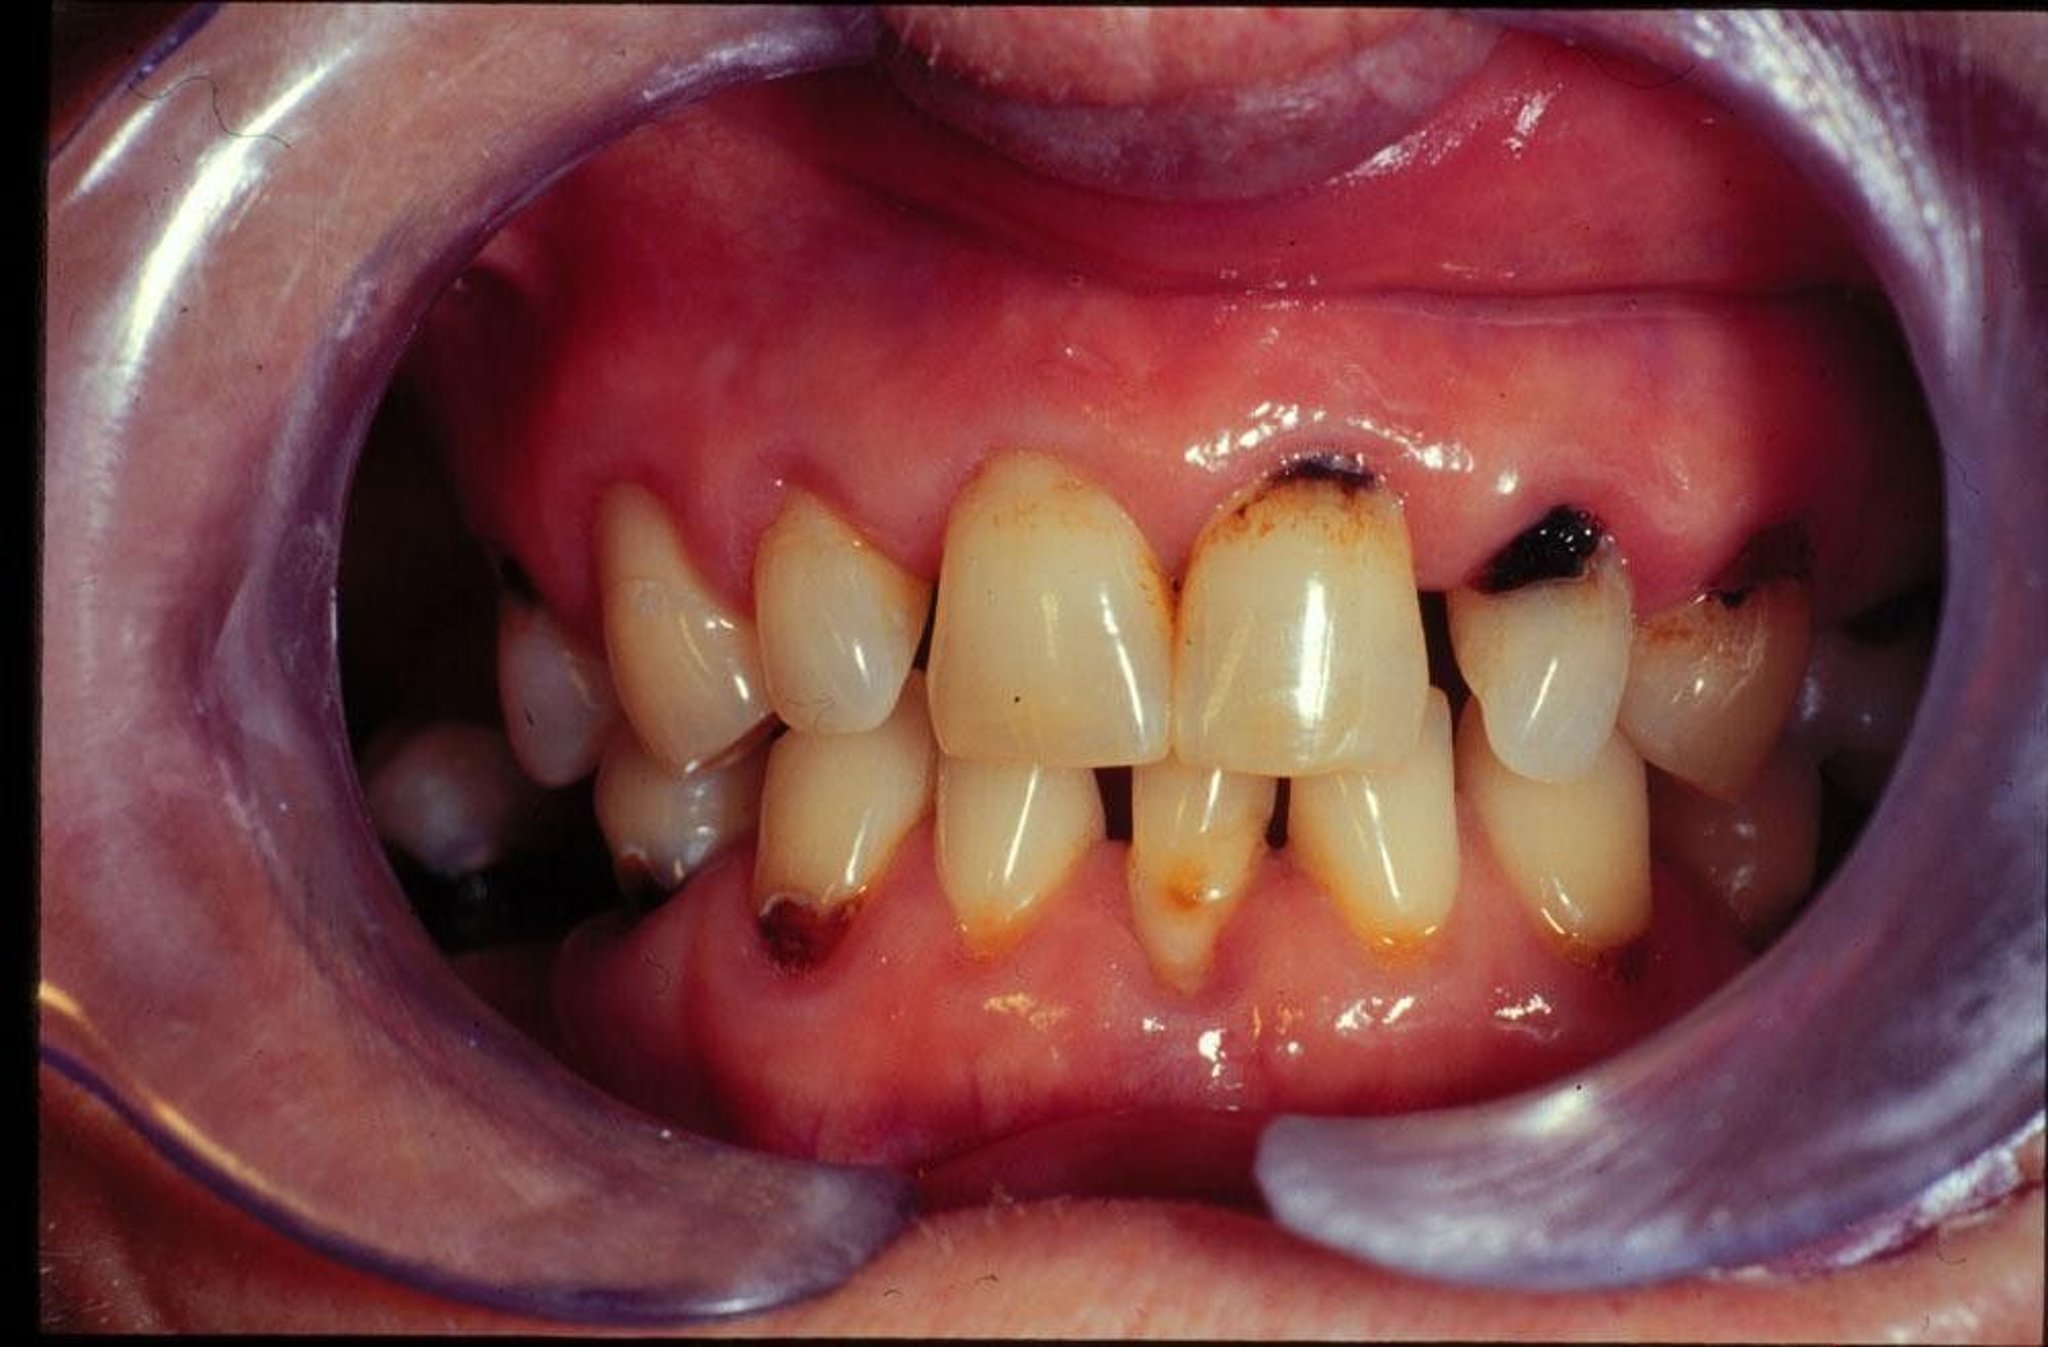

Gigi berlubang

(Karies Gigi)

Gigi berlubang merupakan pembusukan area pada gigi, hasil dari proses yang secara bertahap menghancurkan permukaan luar gigi yang keras (enamel) dan berlanjut ke interior.

Sama halnya dengan penyakit pilek biasa dan penyakit gusi, gigi berlubang (yang disebabkan oleh bakteri) adalah salah satu penderitaan manusia yang paling umum. Apabila gigi berlubang tidak ditangani dengan benar oleh dokter gigi, lubang gigi akan terus membesar. Pada akhirnya, gigi berlubang yang tidak diobati dapat menyebabkan gigi tanggal. Gigi berlubang pada anak-anak dapat menyebabkan gigi susu tanggal terlalu dini, yang mengakibatkan pergeseran gigi di sekitarnya dan dapat mengganggu pertumbuhan gigi permanen.

Pembusukan enamel terjadi secara perlahan. Setelah menembus lapisan gigi kedua—dentin yang agak lebih lunak dan kurang kuat—pembusukan menyebar lebih cepat dan bergerak menuju pulpa, bagian terdalam gigi, yang mengandung saraf dan pasokan darah. Meskipun gigi berlubang dapat memakan waktu 2 atau 3 tahun untuk menembus enamel, gigi berlubang dapat menjalar dari dentin hingga ke pulpa—jarak yang jauh lebih besar—hanya dalam waktu setahun. Dengan demikian, kerusakan akar yang dimulai dari dentin dapat menghancurkan banyak struktur gigi dalam waktu singkat.

Pembusukan akar dimulai pada permukaan yang menutupi akar (sementum) yang telah terpapar oleh gusi yang surut, biasanya pada seseorang yang telah melewati usia pertengahan. Jenis pembusukan ini sering kali disebabkan oleh kesulitan membersihkan area akar, kurangnya aliran air liur yang memadai, diet tinggi gula, atau kombinasi faktor-faktor tersebut. Kerusakan akar gigi dapat menjadi jenis kerusakan gigi yang paling sulit untuk dicegah dan diobati.